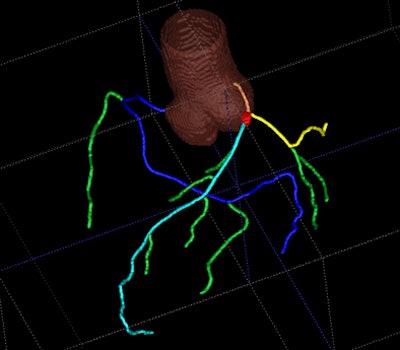

| CAD display shows axial CT image of coronary artery tree. All images courtesy of Dr. Joseph Schoepf. |

The CAD system analyzes the four major coronary arteries: left main (LM), left anterior descending (LAD), left circumflex (LCx), and right coronary artery (RCA), for the presence and location of clinically significant (50% or more) coronary artery stenoses.

The software begins by detecting and segmenting the aorta, and proceeds with the localization of the coronary artery ostia as contrast-filled structures connected to the aorta, Schoepf et al explained. Tubular components are tracked to build the coronary tree, which is then "pruned" of erroneously connected structures.

"The reconstructed coronary artery tree is split into disjoint vessel segments and analysis is performed for each segment separately," the authors wrote. "External boundaries and the lumen of the artery are delineated using an iterative model-based variation approach. Calcified lesions are detected and segmented. Noncalcified plaque is detected as a hypoattenuating area between the external vessel boundary and lumen without calcium."

Parameters are extracted for every cross-section of the vessel segment, including presence and size of plaques, bifurcations, noise level, and extent of artifacts. Finally, the algorithm "matches extracted features to the characteristics of lesions that were used to train the algorithm" and deploys a mark if the lesion features are likely to indicate a significant stenosis, they wrote.